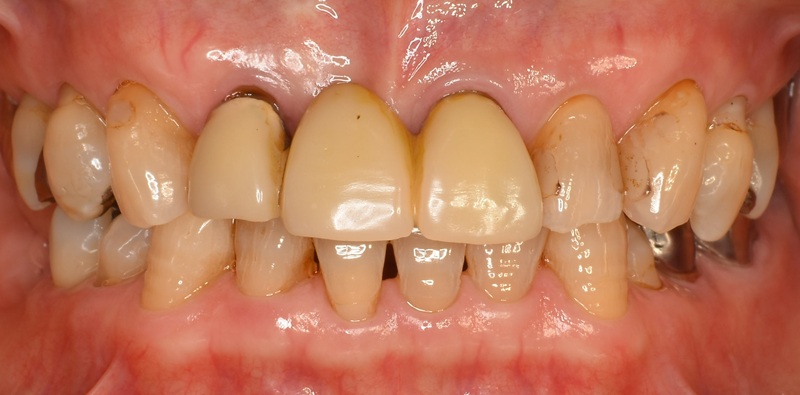

Case3

術前

術後

| 治療名 | 精密根管治療と前歯セラミッククラウンによる審美修復症例 |

|---|---|

| 治療説明 |

以前に治療された前歯の被せ物の見た目を気にされ、再治療をご希望されました。 審美性だけでなく、内部の根管治療まで丁寧に行うことで、将来的なトラブルのリスクを抑えた、長期的に安定した治療結果を目指しました。 |

| 治療回数・期間 | 4回 |

| 副作用とリスク | ・保険診療の銀歯と比べて費用が高額になります。 ・根管治療からクラウン装着までを含めると、治療期間が長くなる傾向があります。 |

| 料金(税込) | 精密根管治療:88,000円×2本 セラミッククラウン:132,000円×2本 合計:440,000円(税込) |